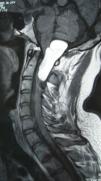

Intradural spinal lipomas with intracranial extension are very rare and are typically diagnosed in childhood. Radical surgical excision usually causes a high rate of morbidity because of the firm adherence between the lipoma and neural tissues. In this report, we present a case of craniocervical intradural intramedullary lipoma in an adult patient. The patient underwent surgery with excision of the mass, leaving a sheet of lipoma on the tumor bed.